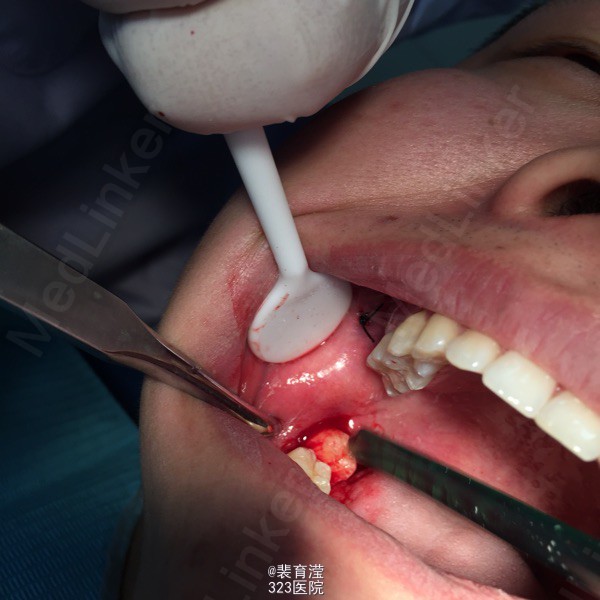

诊断:异物囊肿 右下第三磨牙阻生 处理:1.局麻下切除异物囊肿,缝合,止血。 2.右下第三磨牙局麻下 拔除 搔刮牙槽窝 止血。

随访:口服消炎药 ,止疼药后无不适,一周后拆线 讨论:阻生齿拔除 先去处阻力。